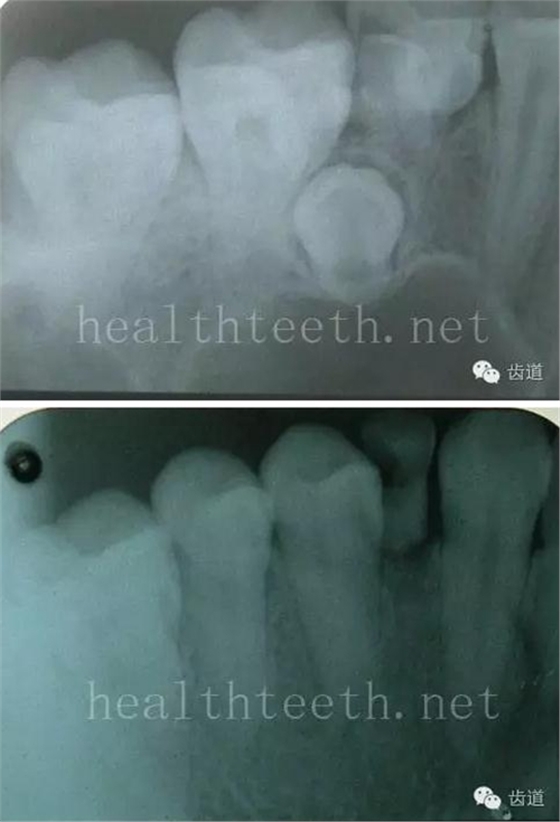

繼發(fā)齲,在充填物四周又發(fā)生的齲齒